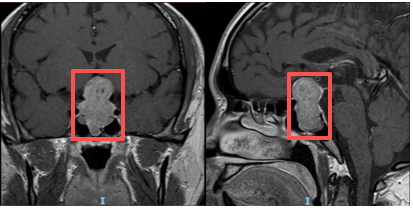

术前垂体增强磁共振可见巨大哑铃型肿瘤

”经头颅CT、磁共振等检查,王海军教授团队确诊李先生为“颅内鞍区占位性病变”,通俗来说,就是颅内长了一个压迫神经的肿物。“当时肿物已经对周围脑组织造成了一定压迫,如果再拖延不积极处理的话,可能会出现失明、脑积水甚者昏迷等严重的并发症。”王海军教授回忆道。”